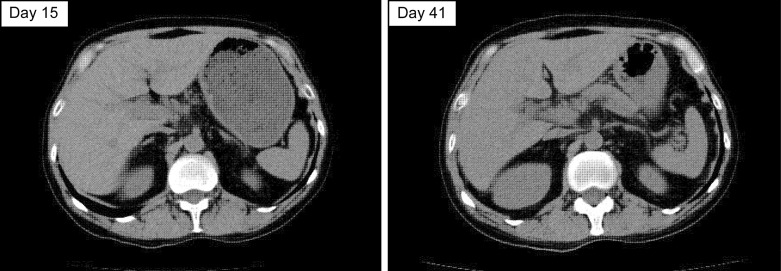

Case presentation: He received carboplatin, pemetrexed, and pembrolizumab as first-line therapy. After four courses, each of the triplet regimen and maintenance therapy with pemetrexed and pembrolizumab, the patient developed immune-related pneumonitis and colitis. Therefore, pemetrexed and pembrolizumab were discontinued, and 0.5 mg/kg/day prednisolone was started. Despite gradual reduction of the prednisolone to 15 mg/day along with resolution of the pneumonitis and colitis, hepatic dysfunction occurred (elevated serum bilirubin and transaminase levels). We made a diagnosis of immune-related hepatitis based on liver biopsy results and negative results for other causes, such as viral infection. We increased the prednisolone dose to 2 mg/kg/day; however, the hepatic dysfunction was not resolved. Upon sequential methylprednisolone pulse therapy (1,000 mg/day), mycophenolate mofetil, and azathioprine treatment, the hepatic dysfunction plateaued but was not resolved. The patient did not respond to steroids for immune-related hepatitis, developed infectious enteritis owing to a compromised state, and died of sepsis on day 107 after diagnosis of immune-related hepatitis.

Conclusion: This case highlights the importance of early diagnosis of steroid-refractory disease, prompt initiation of immunosuppressive agents, and steroid dose reduction in such cases. The changes in liver function during steroid non-response and immunosuppressive drug induction in this case are valuable as a reference for future cases of immune-related adverse event hepatitis.